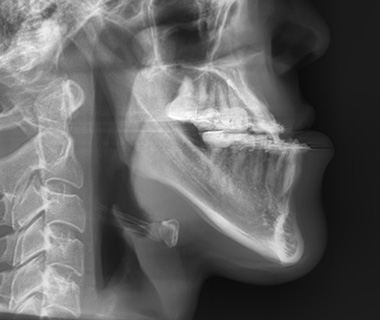

아래턱이 위턱보다 앞으로 나와 보이거나 옆모습에서 턱이 길고 강하게 돌출된 상태를 주걱턱이라 합니다.

이러한 모습은 부정교합을 동반하는 상하악의 길이, 위치 관계 이상(골격성 3급 부정교합) 혹은 턱끝의 과도한 발달로 인해 나타납니다.

턱 전체의 문제로 인한 주걱턱

- 턱 끝이 아니라 위턱·아래턱의 구조적 불균형이 원인

- 반대교합, 하관 과대, 얼굴 비율 문제 동반 가능

- 턱끝 수술만으로는 한계가 있음